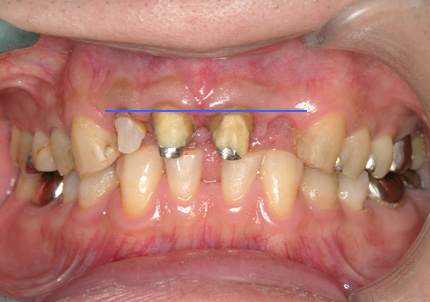

1.初診時口腔内写真(2018年10月)

1.初診時口腔内写真(2014年6月)